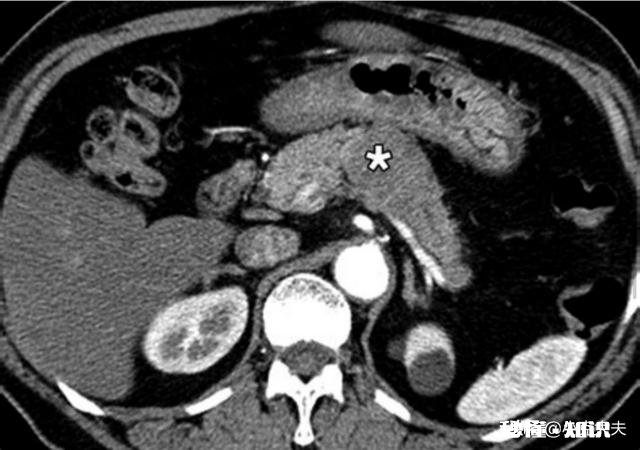

这里我重点介绍下黄疸!胰腺癌的黄疸多半是梗阻性黄疸 。并且多少因为胰头癌对胆管的压迫而造成的梗阻!看图,长在胰头的胰腺癌和胆管是紧紧挨着的,它会压迫胆管,使得胆汁无法排到十二指肠里 。而胰体癌就不会出现这种情况!因此,梗阻性黄疸对胰腺癌,特别是胰头癌的诊断还是很有帮助的!

胰腺体部、尾部的肿瘤主要表现:疼痛、高血糖或低血糖、慢性胰腺炎 , B超、CT等检查可见胰腺体部或尾部出现实质性肿块,部分还会出现胰腺边界模糊、渗出等慢性胰腺炎的表现 。